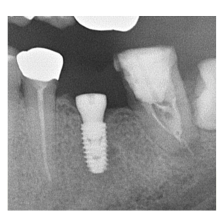

―症例集―

症例一覧